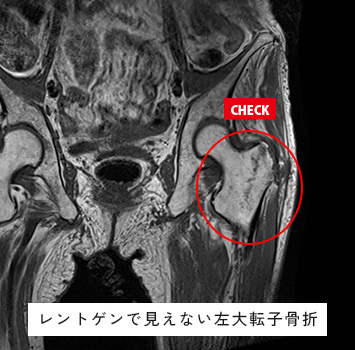

股関節MRIチェック

このような方におすすめします。

• 股関節が痛い

• 股関節が動かしづらい、クリック音がする

• スポーツや仕事で股関節を痛めた、痛みが治らない

筋肉と関節痛みのMRIチェック名古屋なら

レントゲン検査では分からない骨、筋肉、腱、関節唇などの様子が

がたった10分の検査で評価出来ます!

スポーツ選手、左股関節痛が続く、レントゲンで異常なし

転倒後の股関節痛、レントゲンで異常なし